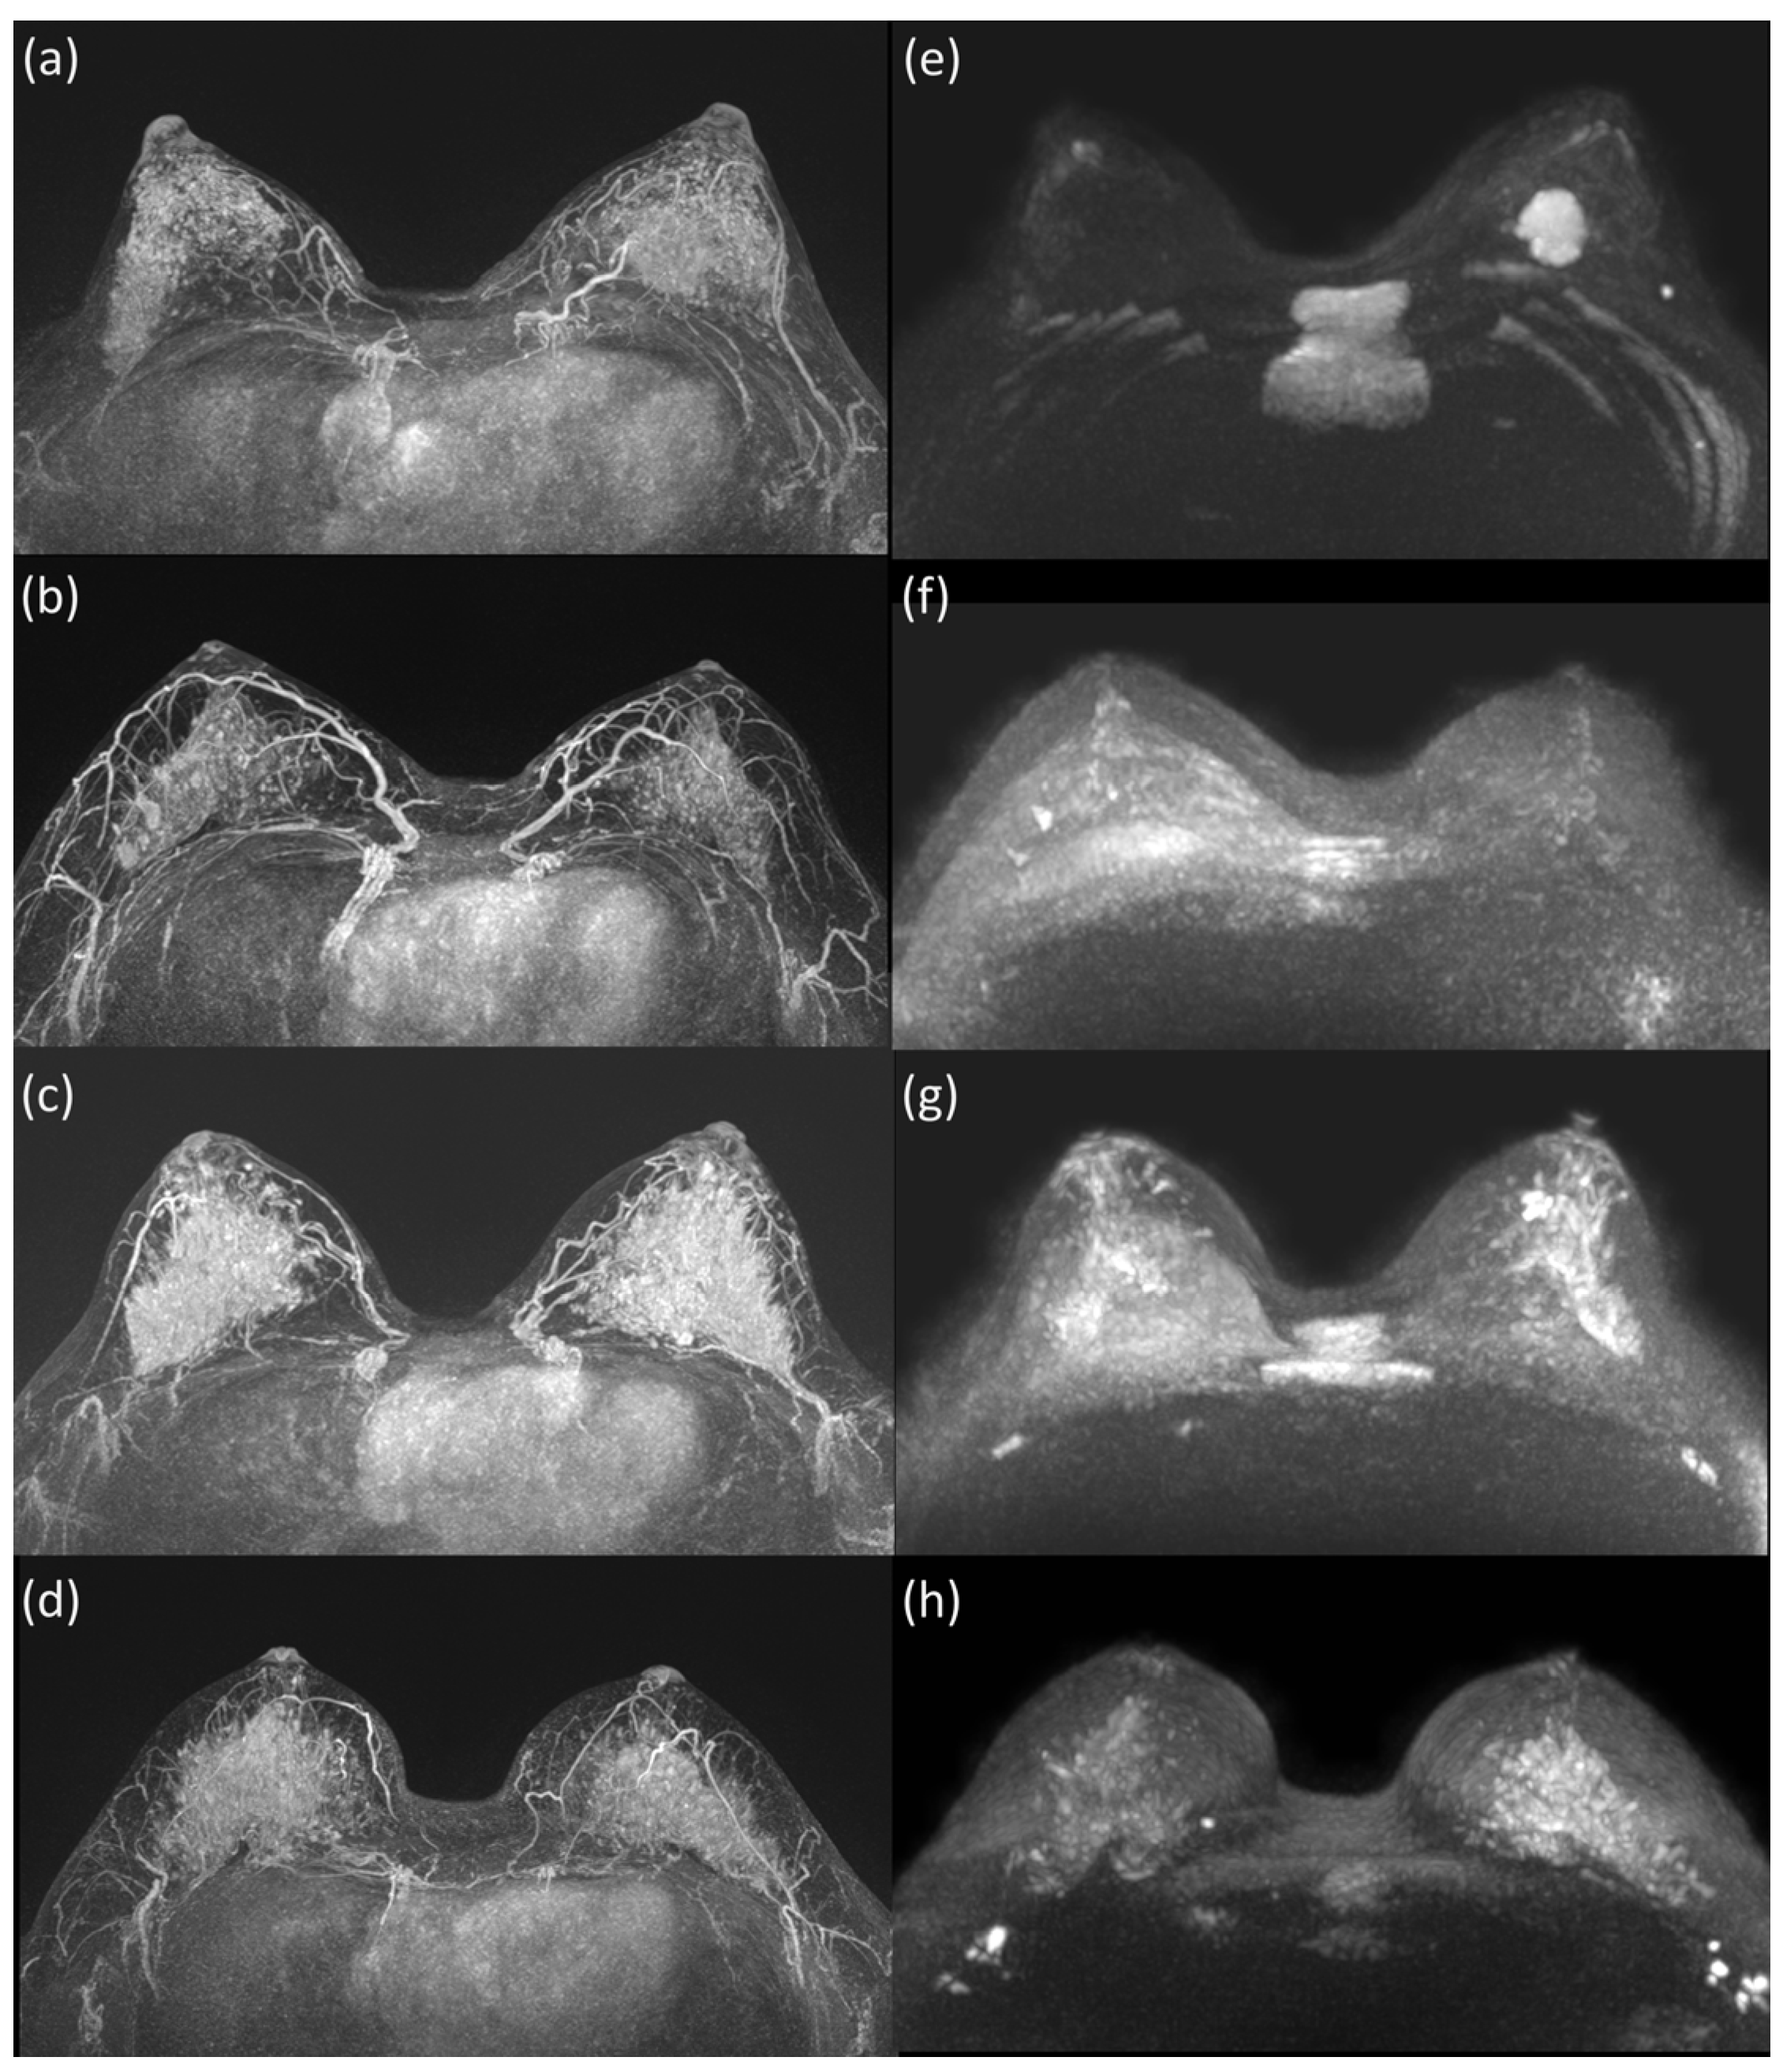

2.3. Image Analysis

| Group | Score | Definition |

|---|---|---|

| Unseen | 1 | absolutely not seen |

| 2 | very subtle visibility | |

| Partially or retrospectively seen | 3 | partial visibility where the lesion was only visible when its location was known (less than 50% visibility) |

| 4 | partial visibility where the lesion was visible when its location was known (more than 50% visibility) | |

| 5 | signified complete visualization of the entire lesion when its location was known, retrospectively | |

| Definitely seen | 6 | visualization of the lesion similar to moderate BPE on CE-MRI, albeit with numerous false-positive lesions |

| 7 | complete confirmation of the lesion similar to moderate BPE on CE-MRI, along with a few false-positive lesions | |

| 8 | easily detected lesion, comparable to mild BPE on CE-MRI (main and daughter lesions) | |

| 9 | very easy identification of the lesion, resembling minimal BPE on CE-MRI | |

| 10 | very easy identification of the lesion, resembling minimal BPE on CE-MRI, with exceptionally clear main and daughter lesions |